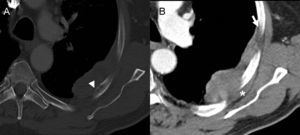

La tomografía computarizada (TC) con contraste intravenoso (fig. 2) muestra una masa periférica, de bordes bien definidos, ángulos obtusos con la pared torácica y realce homogéneo. Presenta invasión de los planos grasos extrapleurales y contacta adelgazando la cortical del arco costal posterior (fig. 2A). No existen nódulos pulmonares ni adenopatías mediastínicas.

Tomografía computarizada con contraste intravenoso, ventana ósea (A) y ventana de partes blandas (B). Masa periférica de bordes bien definidos, realce homogéneo y ángulos obtusos con la pared torácica (flecha). Invade los planos grasos extrapleurales (asterisco) y contacta adelgazando la cortical del arco costal posterior (punta de flecha).

En el estudio de TC (fig. 2), la densidad de la lesión y el realce, independientemente de otras características, descartan el derrame encapsulado y el lipoma/liposarcoma bien diferenciado. El tumor fibroso localizado de la pleura, a pesar de alcanzar gran tamaño, generalmente presenta ángulos agudos con la pared torácica y característicamente no suele presentar invasión de ésta. Por tratarse de una lesión única y de gran tamaño, y por la ausencia de derrame pleural, adenopatías u otras lesiones pulmonares, el diagnóstico de metástasis pleural es muy poco probable. Del mismo modo, la ausencia de derrame pleural y de otros signos de exposición a asbesto, no apoya el diagnóstico de mesotelioma maligno1.